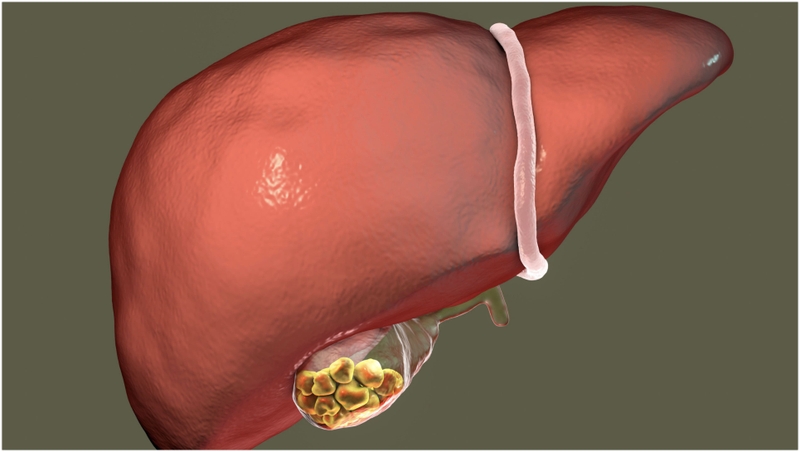

Túi mật, một cơ quan nhỏ có hình quả lê nằm ở dưới gan, là nơi dự trữ dịch mật - một chất lỏng quan trọng giúp tiêu hóa chất béo. Trong quá trình ăn uống, túi mật co bóp để tiết dịch mật vào ruột non, hỗ trợ quá trình tiêu hóa. Vị trí của túi mật thường được xác định ở vùng dưới sườn phải bụng, ngay dưới gan. Khi xuất hiện sỏi, nhiều người lo lắng rằng sỏi túi mật có nguy hiểm không?

Sỏi mật là các viên sỏi hình thành trong túi mật hoặc ống mật, một bệnh lý tuy lành tính nhưng có thể dẫn tới các biến chứng nghiêm trọng nếu không được phát hiện và điều trị tích cực. Khi sỏi gây tắc mật, chúng có thể cản trở dòng chảy của mật tại túi mật hoặc hệ thống đường mật trong và ngoài gan, dẫn đến viêm nhiễm, nhiễm trùng và các hậu quả nguy hiểm khác.